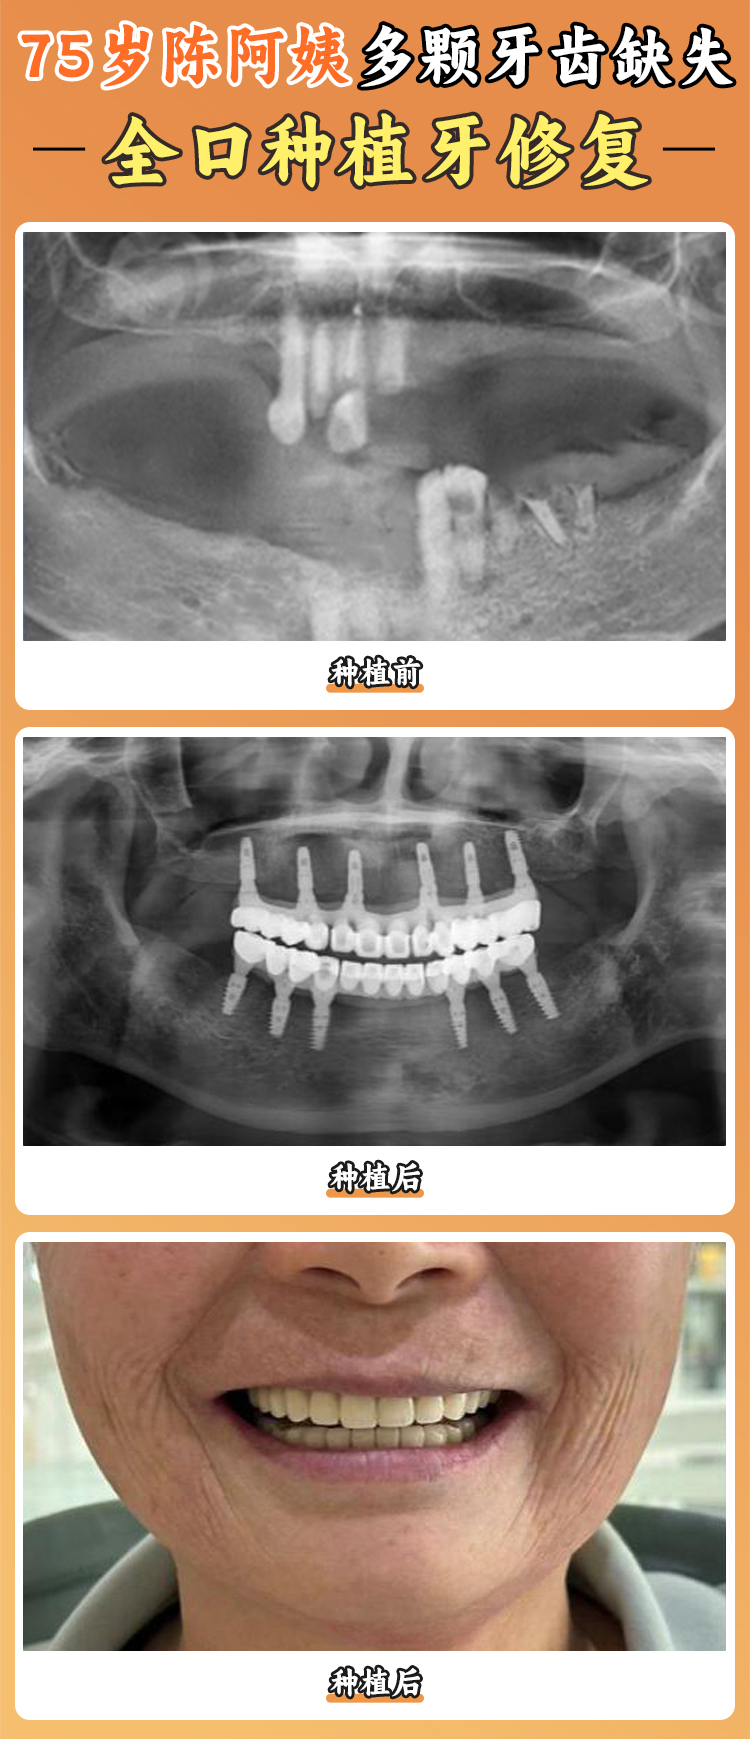

醫(yī)院擁有一支由經(jīng)驗充足的口腔種植醫(yī)師組成的醫(yī)療團隊。這些醫(yī)生就像是經(jīng)驗多的工匠,具備扎實的專科知識和豐富的臨床經(jīng)驗。他們能夠根據(jù)每個患者的不同情況,提供個性化的種植方案,就像為每個人量身定制一件衣服一樣。比如,有的患者牙槽骨條件不太好,醫(yī)生就會采用特殊的種植技術(shù)和方案,確保手術(shù)的可靠性和成效。有一位患者牙齒缺失多年,牙槽骨萎縮重度,其他醫(yī)院都表示治療難度大,但在寧波好牙引領(lǐng)口腔醫(yī)院,醫(yī)生憑借豐富的經(jīng)驗和不錯的技術(shù),成功為他種上了牙齒。